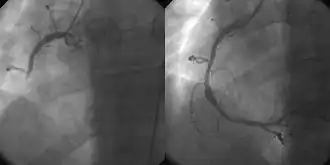

![]() A coronary angiogram showing the circulation in the left coronary artery and its branches. | |